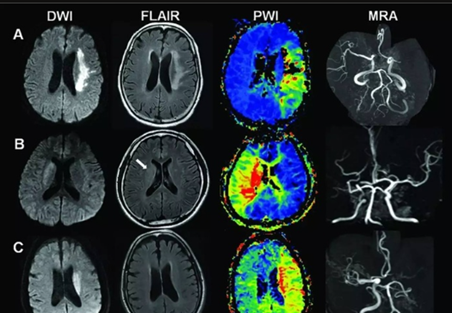

目前,超声、血管造影 (CTA、MRA、DSA)、PET、PET/CT 及 PET/MR 等方法均被应用于动脉硬化和易损斑块特征的分析。

1、超声检查 超声检查可以准确测量CIMT,斑块的位置、形态、大小及回声类型均可被清晰观察。同时,还能分析和判断有无出血和溃疡及斑块纤维帽是否完整,测量管腔狭窄程度,对斑块的稳定性从形态学上进行评价。

3、磁共振血管成像(MRA) 磁共振成像(MRI)通过无创成像方法,可动态观察血管的狭窄程度、斑块的体积大小及演变过程;对斑块成分及表面形态,包括纤维帽破裂和溃疡,加以分析,并对加速粥样病变进程的危险因子加以测评